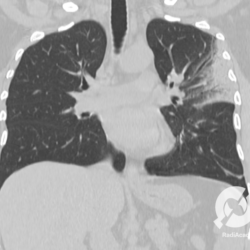

Os agentes etiológicos infecciosos são variados (bactérias, vírus, fungos, parasitas…), mas o que ocorre nos pulmões durante uma infecção por qualquer tipo de agente é a substituição do ar alveolar por secreção (pus, muco, eventualmente sangue ou necrose…) e com isso a manifestação radiográfica vai ser a mesma já que todas estas secreções apresentam a mesma densidade radiográfica: partes moles.

E o nome dado a esta alteração radiográfica que corresponde à substituição do ar alveolar por líquido é a consolidação alveolar.

Uma consolidação alveolar é, por definição, uma opacidade (imagem densa, branquinha) homogênea ou às vezes heterogênea (pela presença de calcificações ou cavidades), de limites mal definidos, exceto quando toca a pleura da parede ou das cissuras pulmonares. É um termo usado tanto em radiografia, como em tomografia computadorizada. Na tomografia, um outro termo é usado: vidro fosco, que é uma opacidade (branquinha mas não tanto como a consolidação), que borra o pulmão mas deixa ver os vasos de permeio (igual bigode de adolescente: dá pra ver todo o fundo).

Nós vamos mostrar aqui um pequeno apanhado de pneumonias de variados agentes, em diversos segmentos e lobos pulmonares, com extensões variadas. O objetivo é identificar o padrão radiológico de consolidação alveolar e não determinar o agente infeccioso, isso vai ser assunto para mais adiante. Aliás já antecipo que é fundamental saber localizar a lesão, porque alguns destes bichos gostam de determinados segmentos, alguns tumores também têm as suas preferências, então localização é fundamental. Se localização não fosse importante, um apartamento na beira do mar sairia o mesmo preço de um apartamento de frente pra BR-101, concordam?